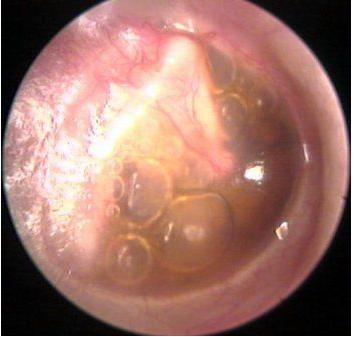

西安新城中大耳鼻喉医院医生表示:用耳内窥镜检查病人的耳部,会发现鼓膜内陷,鼓膜呈淡黄或橙红色,有时透过鼓膜可见气泡。

上面这张显示的是一例慢性分泌性中耳炎的鼓膜图片,鼓膜不透明,如毛玻璃状,鼓膜紧张部有扩张的微血管,多提示鼓室内的为非常粘稠的积液。想知道自身的中耳炎是哪种类型可询问在线咨询